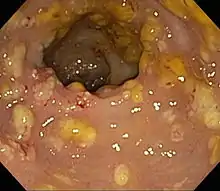

![]() | |

Pathological specimen showing pseudomembranous colitis | |

Prior to the advent of tests to detect C. difficile toxins, the diagnosis most often was made by colonoscopy or sigmoidoscopy. The appearance of "pseudomembranes" on the mucosa of the colon or rectum is highly suggestive, but not diagnostic of the condition.[45] The pseudomembranes are composed of an exudate made of inflammatory debris, white blood cells. Although colonoscopy and sigmoidoscopy are still employed, now stool testing for the presence of C. difficile toxins is frequently the first-line diagnostic approach. Usually, only two toxins are tested for—toxin A and toxin B—but the organism produces several others. This test is not 100% accurate, with a considerable false-negative rate even with repeat testing.[46]